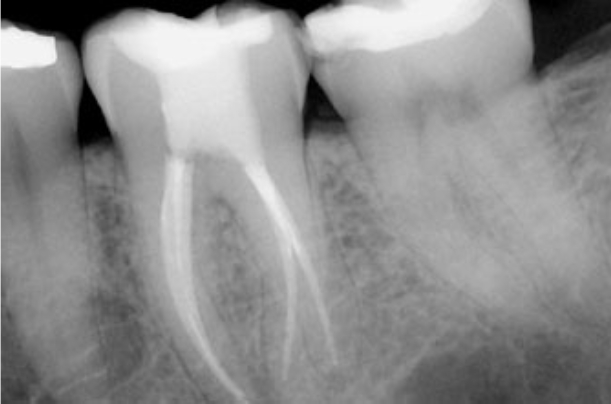

Root Canal Therapy Step by Step

What To Expect When Having A Root Canal in Mexico?